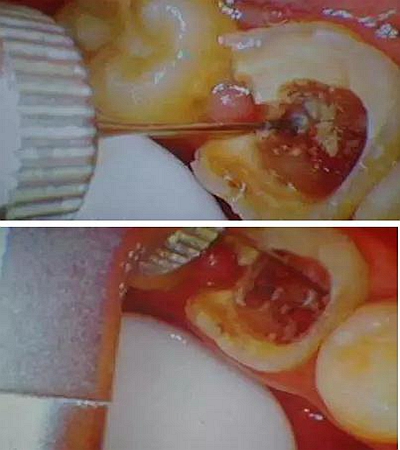

初診時口內(nèi)照片:

因為腐質(zhì)比較多用剔挖器處理:

剔挖器進(jìn)一步處理后見到底穿部位:根管挖匙派上用場,穿孔部位有少許膿液。